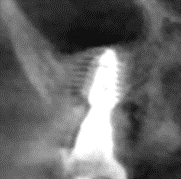

3/ Bước 3: Giai đoạn cấy ghép implant

Chuẩn bị răng tạm cố định 1 ngày sau phẫu thuật

Gắn răng tạm cố định 1 ngày sau phẫu thuật

X-Quang ngay sau gắn răng tạm cố định

Sau 6 tháng lấy dấu làm phục hình chính thức.